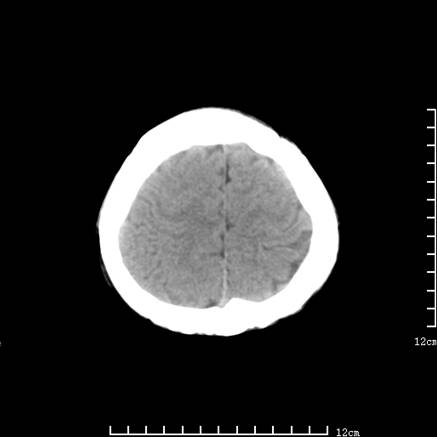

以下是引用jiajie在2008-9-5 22:25:00的发言:[br]男,22岁,头痛1月余。脑室、脑池内病变ct值约-120hu。[br][br]双侧侧脑室内低密度影充填,出现脑脊液脂肪平面,脑池内亦可见弥散分布的斑点状低密度影,脑室脑池未见明显扩大。[br]考虑胆脂瘤破裂后内容物进入脑脊液。